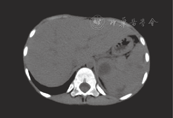

入院后予美罗培南10 mg/(kg·次),每8小时1次,治疗4 d后体温逐渐正常,检查结果发现患儿同时存在脓毒症及不典型化脓性脑膜炎,入院第6天加用哌拉西林他唑巴坦共治疗10 d,患儿体温稳定,复查PCT、CRP等炎症指标均有所下降,复查血培养阴性,并完成化脓性脑膜炎治疗疗程,骨髓穿刺排除血液系统疾病,但多次复查血常规均提示WBC明显升高,(23~27)×109/L,逐渐出现肝脏功能损伤,入院第29天复查谷丙转氨酶398.05 U/L,谷草转氨酶602.47 U/L。复查腹部彩超:肝脾大,脾脏多发低回声区:脓肿(?),见图1。CT示脾脏内多发结节灶,似见环形强化,肝脾稍大,考虑为多发性脓肿(图2)。因考虑患儿年龄小,脾脏脓肿散在分布,穿刺及手术治疗风险大,患儿体温稳定,一般情况好,体重有所增加,继续保守治疗,于入院第50天停用美罗培南,改用哌拉西林他唑巴坦。入院第53天患儿再次发热,复查血常规WBC升高至36.18×109/L,N 0.465,再次使用美罗培南、伏立康唑预防真菌感染,并予丙种球蛋白、胸腺肽加强支持治疗,患儿一直发热,咳嗽加重,美罗培南再次使用8 d后,根据痰培养(嗜麦芽糖寡养单胞菌)及药敏结果改用哌拉西林他唑巴坦,复查腹部B超提示脾脏脓肿有所好转,患儿发热、咳嗽无好转,复查胸部CT提示胸腔积液,外周血WBC继续升高,达45.54×109/L、N 0.565,入院第72天起加用万古霉素,经3次抽胸水、抗感染治疗(痰培养:阴沟肠杆菌,对头孢吡肟敏感)及纤支镜灌洗,第97天起患儿体温逐渐稳定,复查腹部B超脾脓肿消退,WBC(23~29)×109/L,临床症状基本消退,1个月后复查腹部B超未见脓肿复发。

实验室检查普遍提示WBC升高,有文献报道88.8%的脾脓肿患者WBC升高[2]。我们报道的两例均有此表现,第1例患儿在体温控制、病情好转的情况下,WBC仍处于明显升高状态,甚至在脾脏脓肿消失、继发肺部病变好转后1个月WBC计数仍然升高,同时伴有红细胞沉降率、CRP、PCT等其他炎性指标升高,存在明显的全身炎症反应;第2例患儿直到脾切除、感染病灶清除后WBC才逐步恢复正常。腹部B超是最常用于脾脓肿诊断的方法,其简单、无创,可直观地显示脾脏内低回声或无回声暗区,边缘不平整,腔壁较厚,对早期诊断脾脓肿具有重大意义,CT/MRI检查准确度高,敏感性及特异性均可达90%,确诊依靠穿刺术或穿刺液培养。本报道2例患儿腹部B超、CT均提示脾脓肿,但因脓肿小、多发,故未考虑穿刺、引流及置管冲洗等。